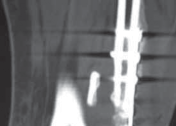

12. If the fracture fragment is of sufficient size, an antiglide plate (one-third tubular) may be placed with undercon-touring of the plate to provide a satisfactory buttress effect (

TECH FIG 6

).

--- TECH FIG 6 • Postoperative AP and lateral radiographs demonstrating posterior plating of the tibia to buttress the posterior malleolar fracture fragment. ### TECHNIQUES